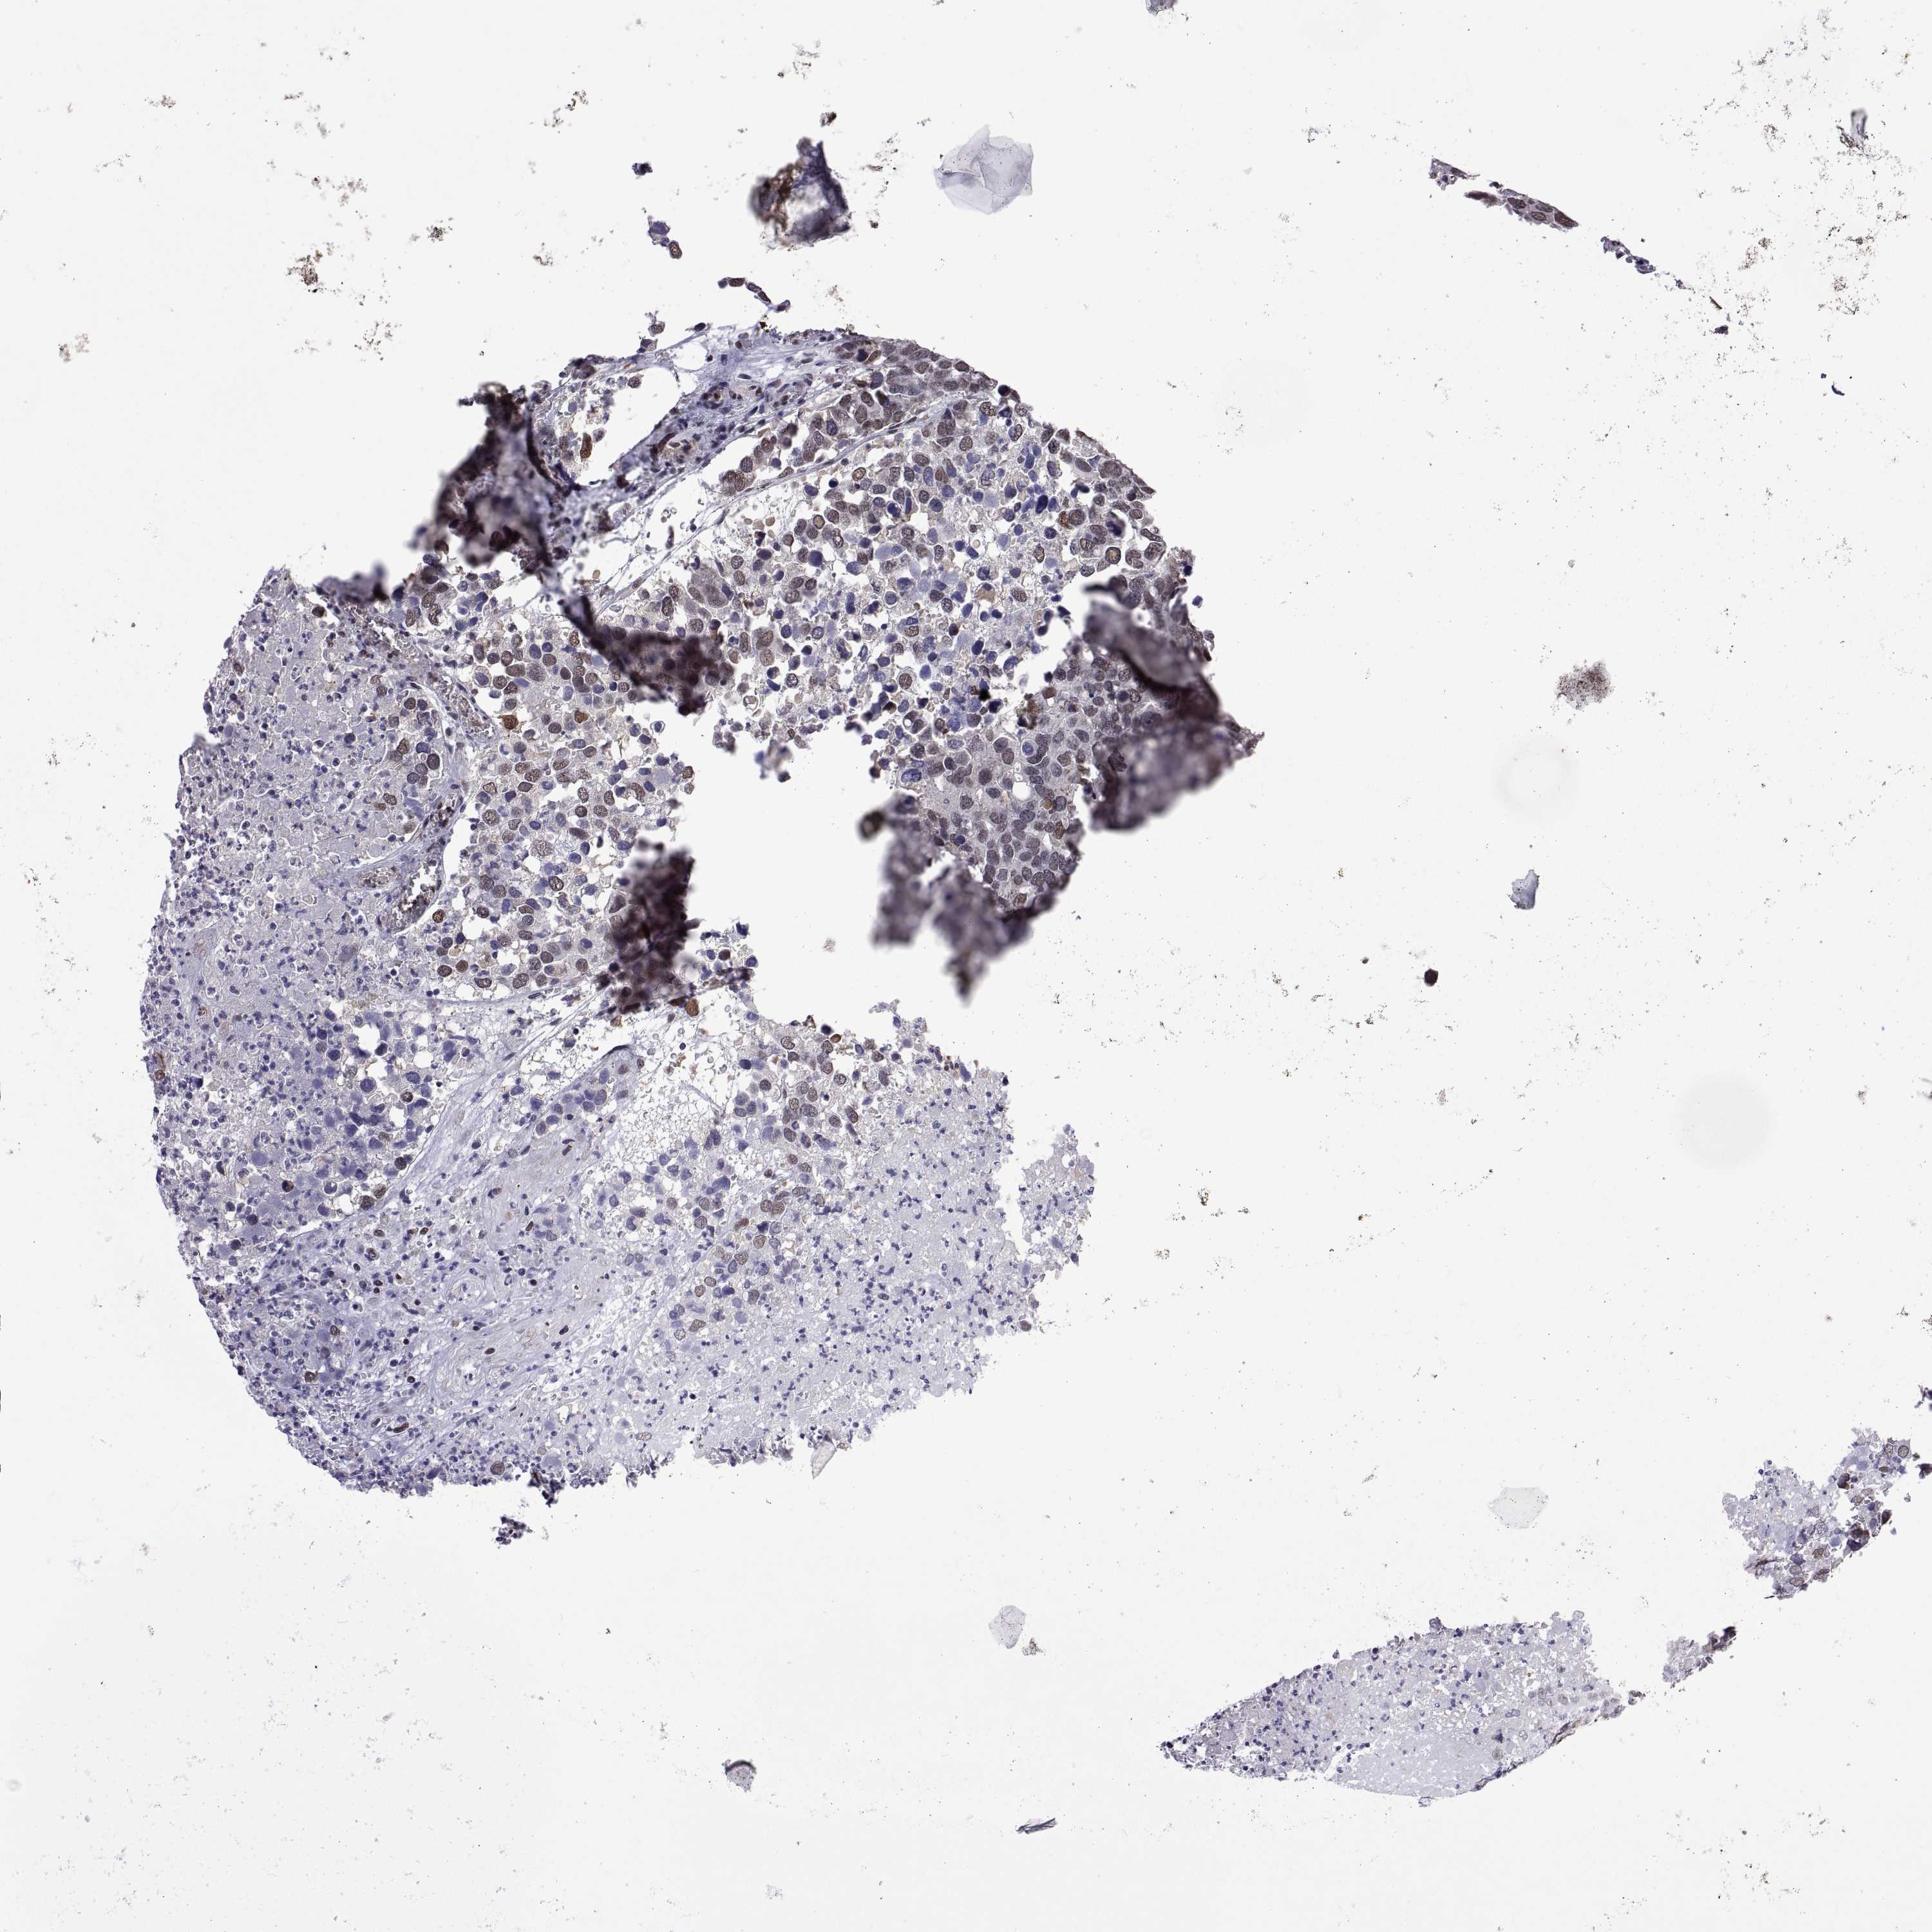

CANCER BREAST CANCER Show tissue menu

BRCA TCGA BRCA VALIDATION PROTEIN EXPRESSION

Breast cancer

Human cancer

Breast invasive carcinoma